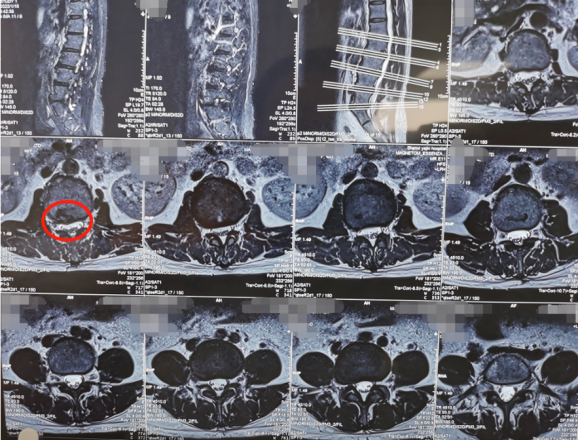

术前影像学资料

当时由熊东主任接诊后,发现他腰5骶1椎间盘突出,并且已经严重压迫神经根,这种情况建议尽快进行手术解压,于是就尽快为他做了非常微创的椎间孔镜手术。手术效果非常好,这次来复查时健步如飞,走路和正常人完全一样,腿部疼痛已经消失。